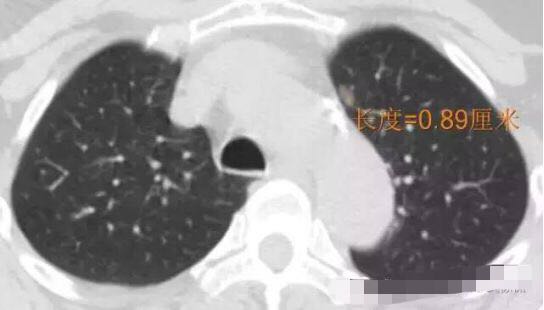

病例2

随访3年,GGO直径基本没有变化

2013年12月

2014年7月

2015年5月

2016年10月